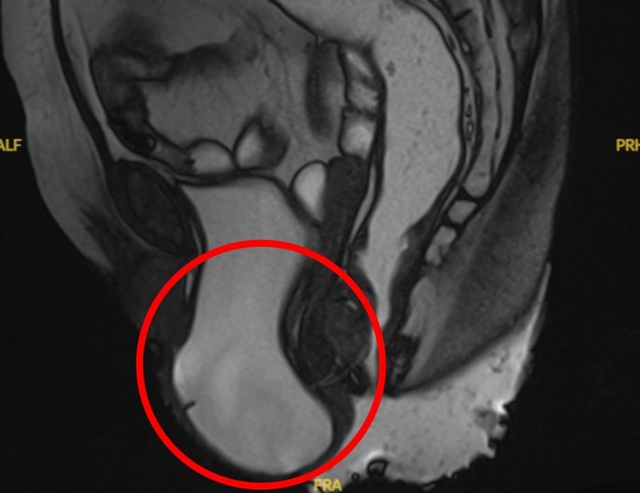

Khi đến khám tại Phòng khám khoa Ngoại Tiết Niệu – BVĐK Xuyên Á Long An, bà T. đã được các bác sĩ thăm khám và chụp MRI sàn chậu. Kết quả cho thấy bà mắc sa sàn chậu độ III, sa bàng quang độ III và sa tử cung độ II.

Nhận định tình trạng của bà T. đã ở mức độ nặng, gây nhiều ảnh hưởng tới sức khoẻ cũng như tâm lý người bệnh, các bác sĩ đã chỉ định phẫu thuật nội soi khâu treo cố định sàn chậu vào mỏm nhô xương cùng. "Phương pháp này không chỉ giúp phục hồi cấu trúc và chức năng của sàn chậu, cải thiện rõ rệt các triệu chứng khó chịu, mang lại chất lượng sống tốt hơn cho người bệnh" – BS. CKI. Lê Thanh Phong chia sẻ.